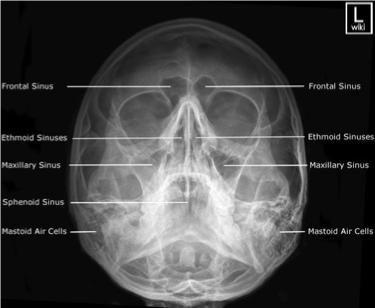

PA Axial of the Frontal and Ethmoidal Sinuses - Caldwell Method

PA axial of the frontal and ethmoidal sinuses (Caldwell Method)